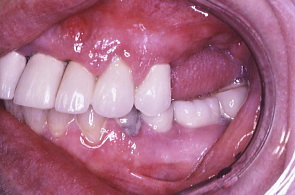

歯科医院指導の下、患者の熱心な歯磨きと衛生士の機械的清掃により、初診時に比べ歯ぐきが引き締まった。